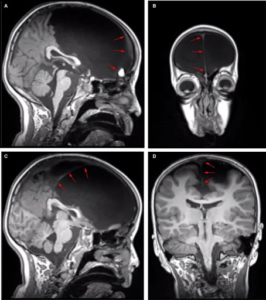

The frontal lobes are one of the most complex brain structures involved in both domain-general and specific functions. The goal of this work was to assess the anatomical and cognitive affectations from a unique case with massive bilateral frontal affectation. We report the case of GC, an eight-year old child with nearly complete affectation of bilateral frontal structures and spared temporal, parietal, occipital, and cerebellar regions. We performed behavioral, neuropsychological, and imaging (MRI, DTI, fMRI) evaluations. Neurological and neuropsychological examinations revealed a mixed pattern of affected (executive control/abstraction capacity) and considerably preserved (consciousness, language, memory, spatial orientation, and socio-emotional) functions. Both structural (DTI) and functional (fMRI) connectivity evidenced abnormal anterior connections of the amygdala and parietal networks. In addition, brain structural connectivity analysis revealed almost complete loss of frontal connections, with atypical temporo-posterior pathways. Similarly, functional connectivity showed an aberrant frontoparietal network and relative preservation of the posterior part of the default mode network and the visual network. We discuss this multilevel pattern of behavioral, structural, and functional connectivity results. With its unique pattern of compromised and preserved structures and functions, this exceptional case offers new constraints and challenges for neurocognitive theories.